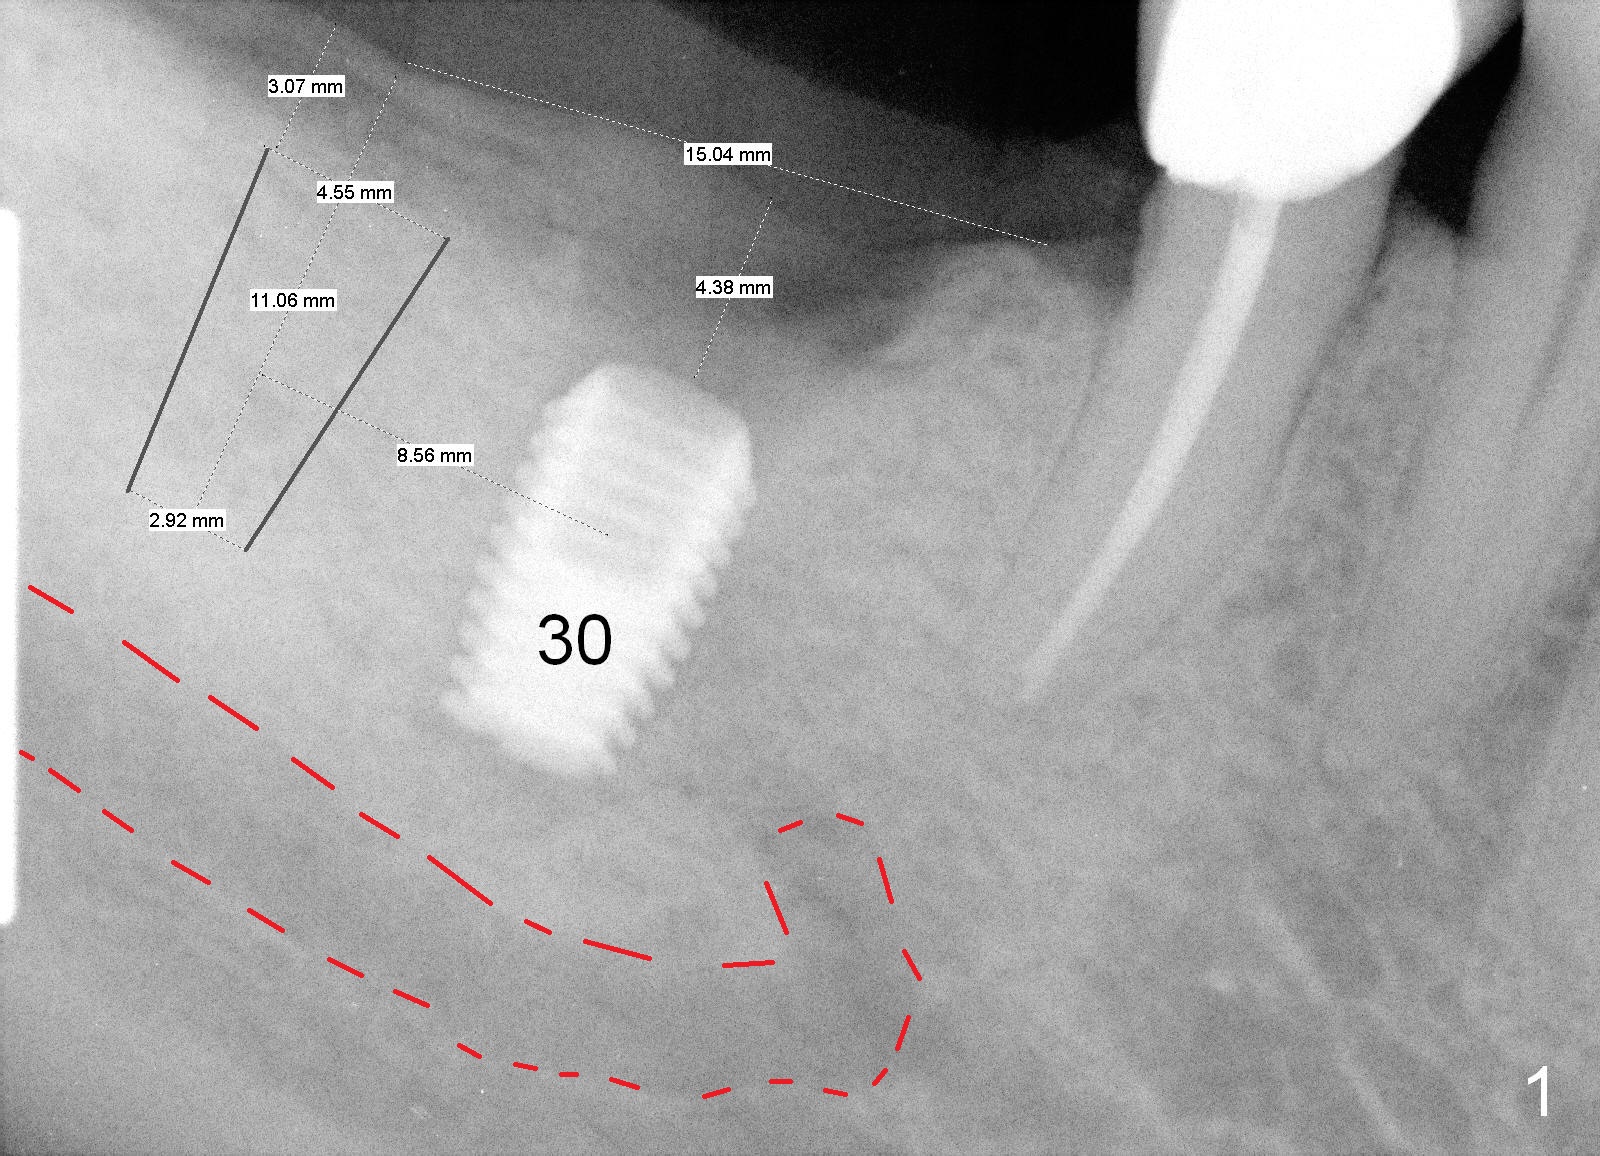

A 62-year-old man has had a Bicon abutment supported crown at #30 for nearly 2 years (Fig.1, 2 (when Tatum implant was failing)).  Probably due to the fact that the implant is placed distally, there is food impaction mesially.  Prior to #31 implant placement, the crown/abutment will be removed with the universal forceps and reseated.  Pick up impression will be taken and sent to lab for mesial gap closure with porcelain.  Take photos to show the gap preop.

Before crown removal, use the 3.5 mm (vs. normally 5 mm) implant spacer and #15 to mark an entrance point for #31 implant (make a cross over the crestal gingiva).  After crown removal, insert a 3 mm Guide Pin into #30 implant well as a parallel pin.  Use 2 mm pilot drill to start osteotomy through the cross and then make incision.  While drilling and reaming, pay attention to the submandibular fossa (Fig.3 SF) and the Inferior Alveolar Canal (orange).  When a 4.5x8 mm implant is placed, place abutments and make splinted provisional.